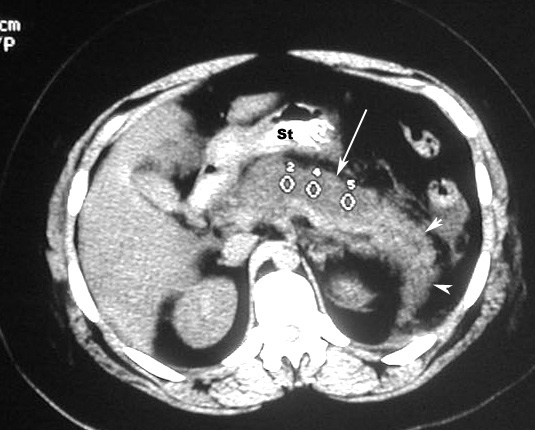

Acute Pancreatitis

Phlegmon / Inflammatory mass

• White arrowheads: Phlegmon

• Black arrowhead: Pancreatic calcification

• Large Arrow: Peripancreatic fascial infiltration

St: Stomach